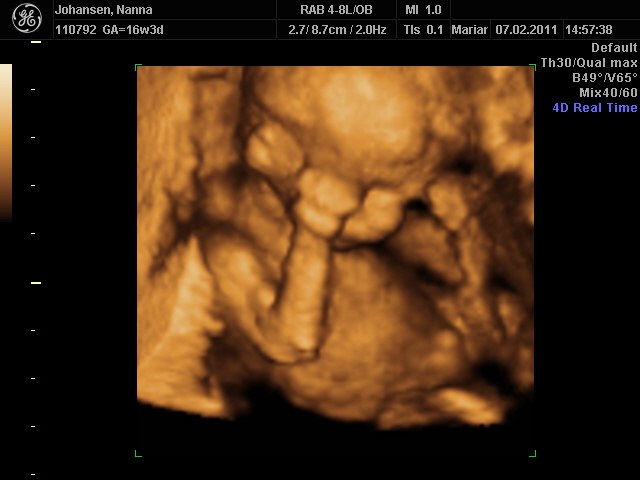

vi venter os en lille søn han er super dejlig

Det er tydeligt :-)

Der er ingen tvivl på at det er en dreng Tillykke

Ej hvor er det bare et godt scanningsbillede det er helt vildt sødt og fingerne inde i munden

er det 3D billede ? tillykke med at du os venter en søn - sikke mange der ska have en lille knægt